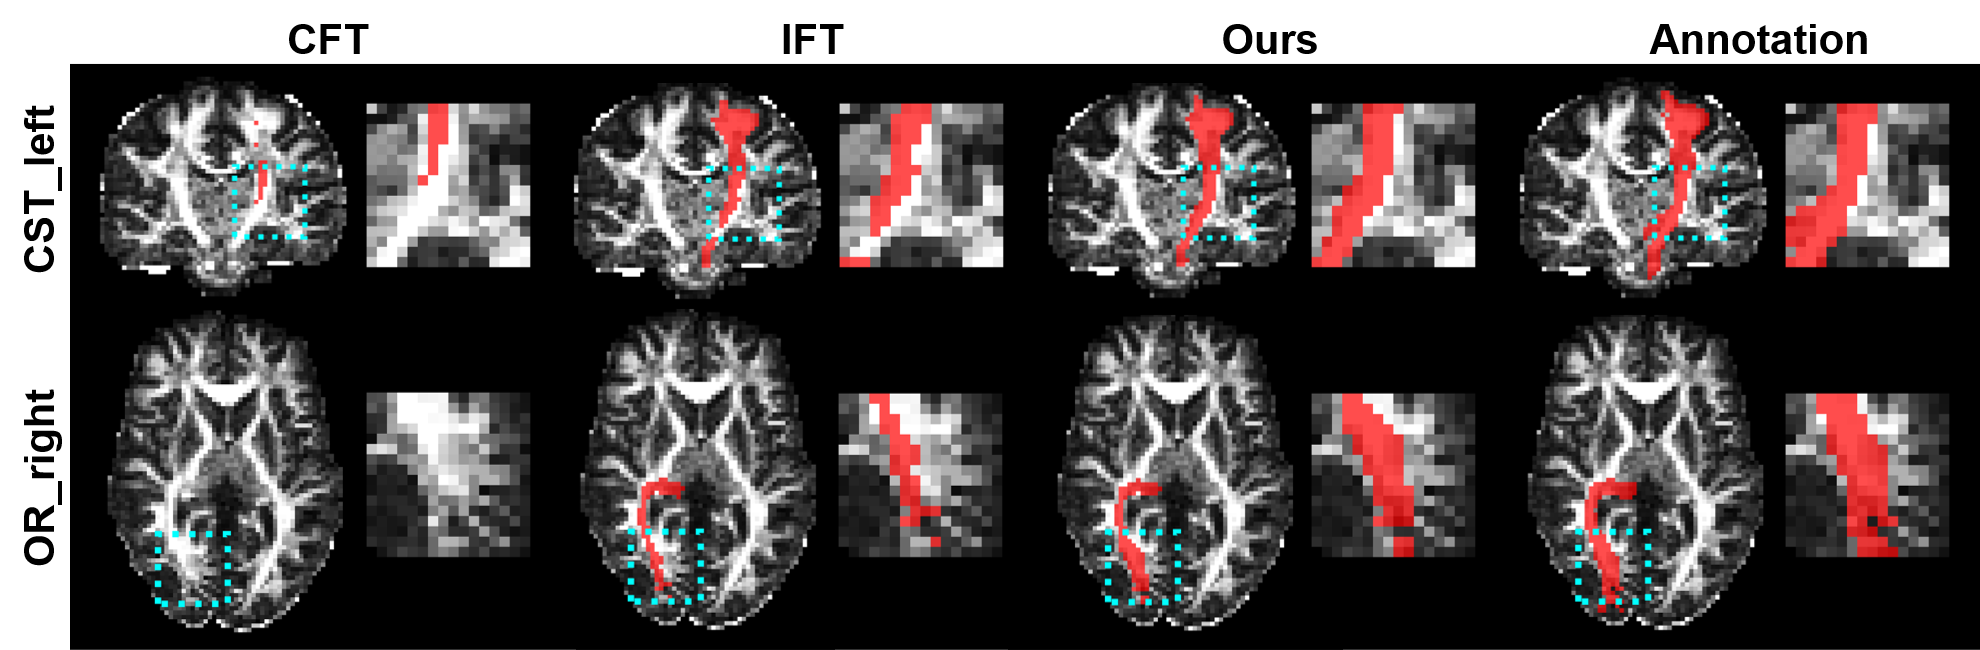

Figure 1: Examples of the segmentation results (red) for novel WM tracts. The results were obtained in the case of CQ1 and are overlaid on the fractional anisotropy maps. The annotations are also shown for reference. Note the highlighted regions and their zoomed views for comparison.

We first qualitatively evaluated the proposed method. Examples of the segmentation results for novel WM tracts are shown in Fig. 1 for the proposed and competing methods, where the annotations are also displayed for reference. For demonstration, here we show the results obtained in the case of CQ1 for CST_left and OR_right. We can see that the segmentation results of our method better resemble the annotations than those of the competing methods.